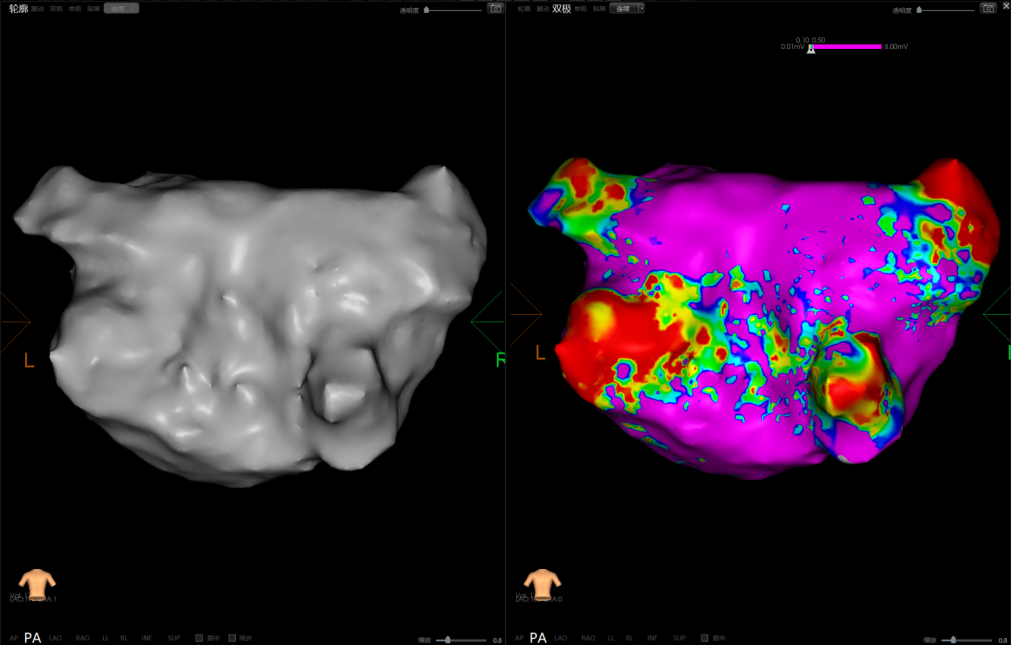

手术在介入导管室的通力配合下进行,姜馨主任、薛建颖主治医师、刘成峰医师密切配合,术中通过右侧股静脉送入心腔内超声(ICE)至右心房,排除左房血栓后成功指导精准房间隔穿刺,沿可调弯鞘管送入锦江心脏脉冲电场消融导管至左房,构建左房三维解剖模型并行基质标测,标测显示左房基质尚可,分别行左侧、右侧肺静脉消融。消融参数:1800v、400ms、400μs,共放电消融148次(消融左上肺静脉时转复为窦性心律),验证双肺静脉均隔离。术后重新标测显示所有肺静脉均已急性阻滞,消融效果理想,肺静脉前庭损伤范围也达到了预期的标准,同时ICE监测未见明显心包积液。手术仅用时30分钟,时间明显缩短,手术过程精准高效。术后患者恢复情况良好并顺利出院。术后1月复查心电图提示窦性心律,心脏超声提示心脏较前明显缩小,收缩功能明显改善,射血分数由25%提升至40%,心功能标记物NT-proBNP 恢复正常,仅54pg/ml。

图3 术中三维建模及电压标测